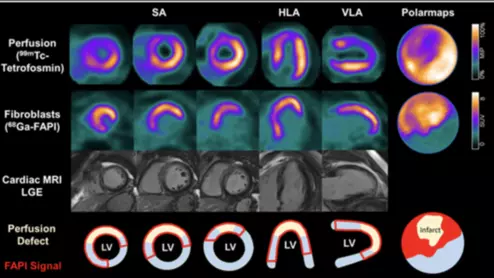

SNMMI Image of the Year 68Ga-FAPI-46 PET/CT heart attack acute myocardial infarction

More and more imaging researchers are starting to examine the potential of using fibroblast activation protein inhibitors (FAPI) to manage patients with suspected cardiovascular disease.